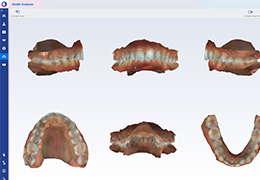

Performs 3D reconstruction and volume rendering.

Instant and interactive surface extraction and export to STL and PLY formats.